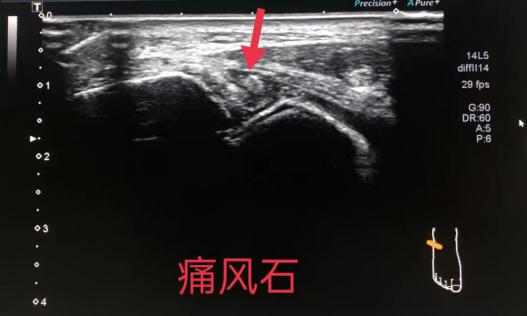

1、关节疾患:关节腔积液(血)、滑膜增厚(非特异性)、游离体、痛风性关节炎、类风湿性关节炎疗效监测、检出部分骨侵蚀、骨赘、退行性关节病(骨关节炎)等。